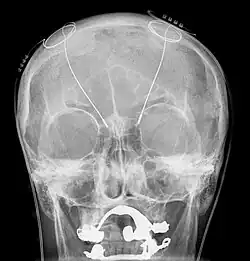

Als Steuerelement dient ein kleiner batteriegetriebener und chipgesteuerter Impulsgeber, der unter der Haut der Brustmuskulatur oder am Oberbauch eingesetzt wird. Die Elektroden werden durch kleine Löcher in der Schädeldecke in die Zielregion der Basalganglien der linken und rechten Gehirnhälfte eingeführt.

Für die chronische Hirnstimulation werden dem Patienten mit einem stereotaktischen Zielgerät eine oder zwei dünne Elektroden implantiert, die über subkutan verlegte Kabel mit einem Impulsgeber im Bereich der Brust oder dem Oberbauch verbunden sind. Dieser Impulsgeber gibt dauerhaft elektrische Impulse an die Zielregion im Gehirn ab, wodurch diese – je nach Stromfrequenz – entweder deaktiviert oder stimuliert werden kann.

Die Operation erfolgt in zwei Schritten. Im ersten werden dem Patienten in einer stereotaktischen Operation kleine Löcher in die Schädeldecke gebohrt, durch die die Elektroden in das Gehirn eingeführt werden. Dabei ist der Patient in der Regel bei vollem Bewusstsein. Nur so kann mit Hilfe von Teststimulationen die Wirksamkeit der einzelnen Elektroden und damit deren exakte Lage überprüft werden. Der Impulsgenerator (Hirnschrittmacher) wird entweder während dieses Eingriffs oder in einer zweiten, kürzeren Operation am Folgetag implantiert.